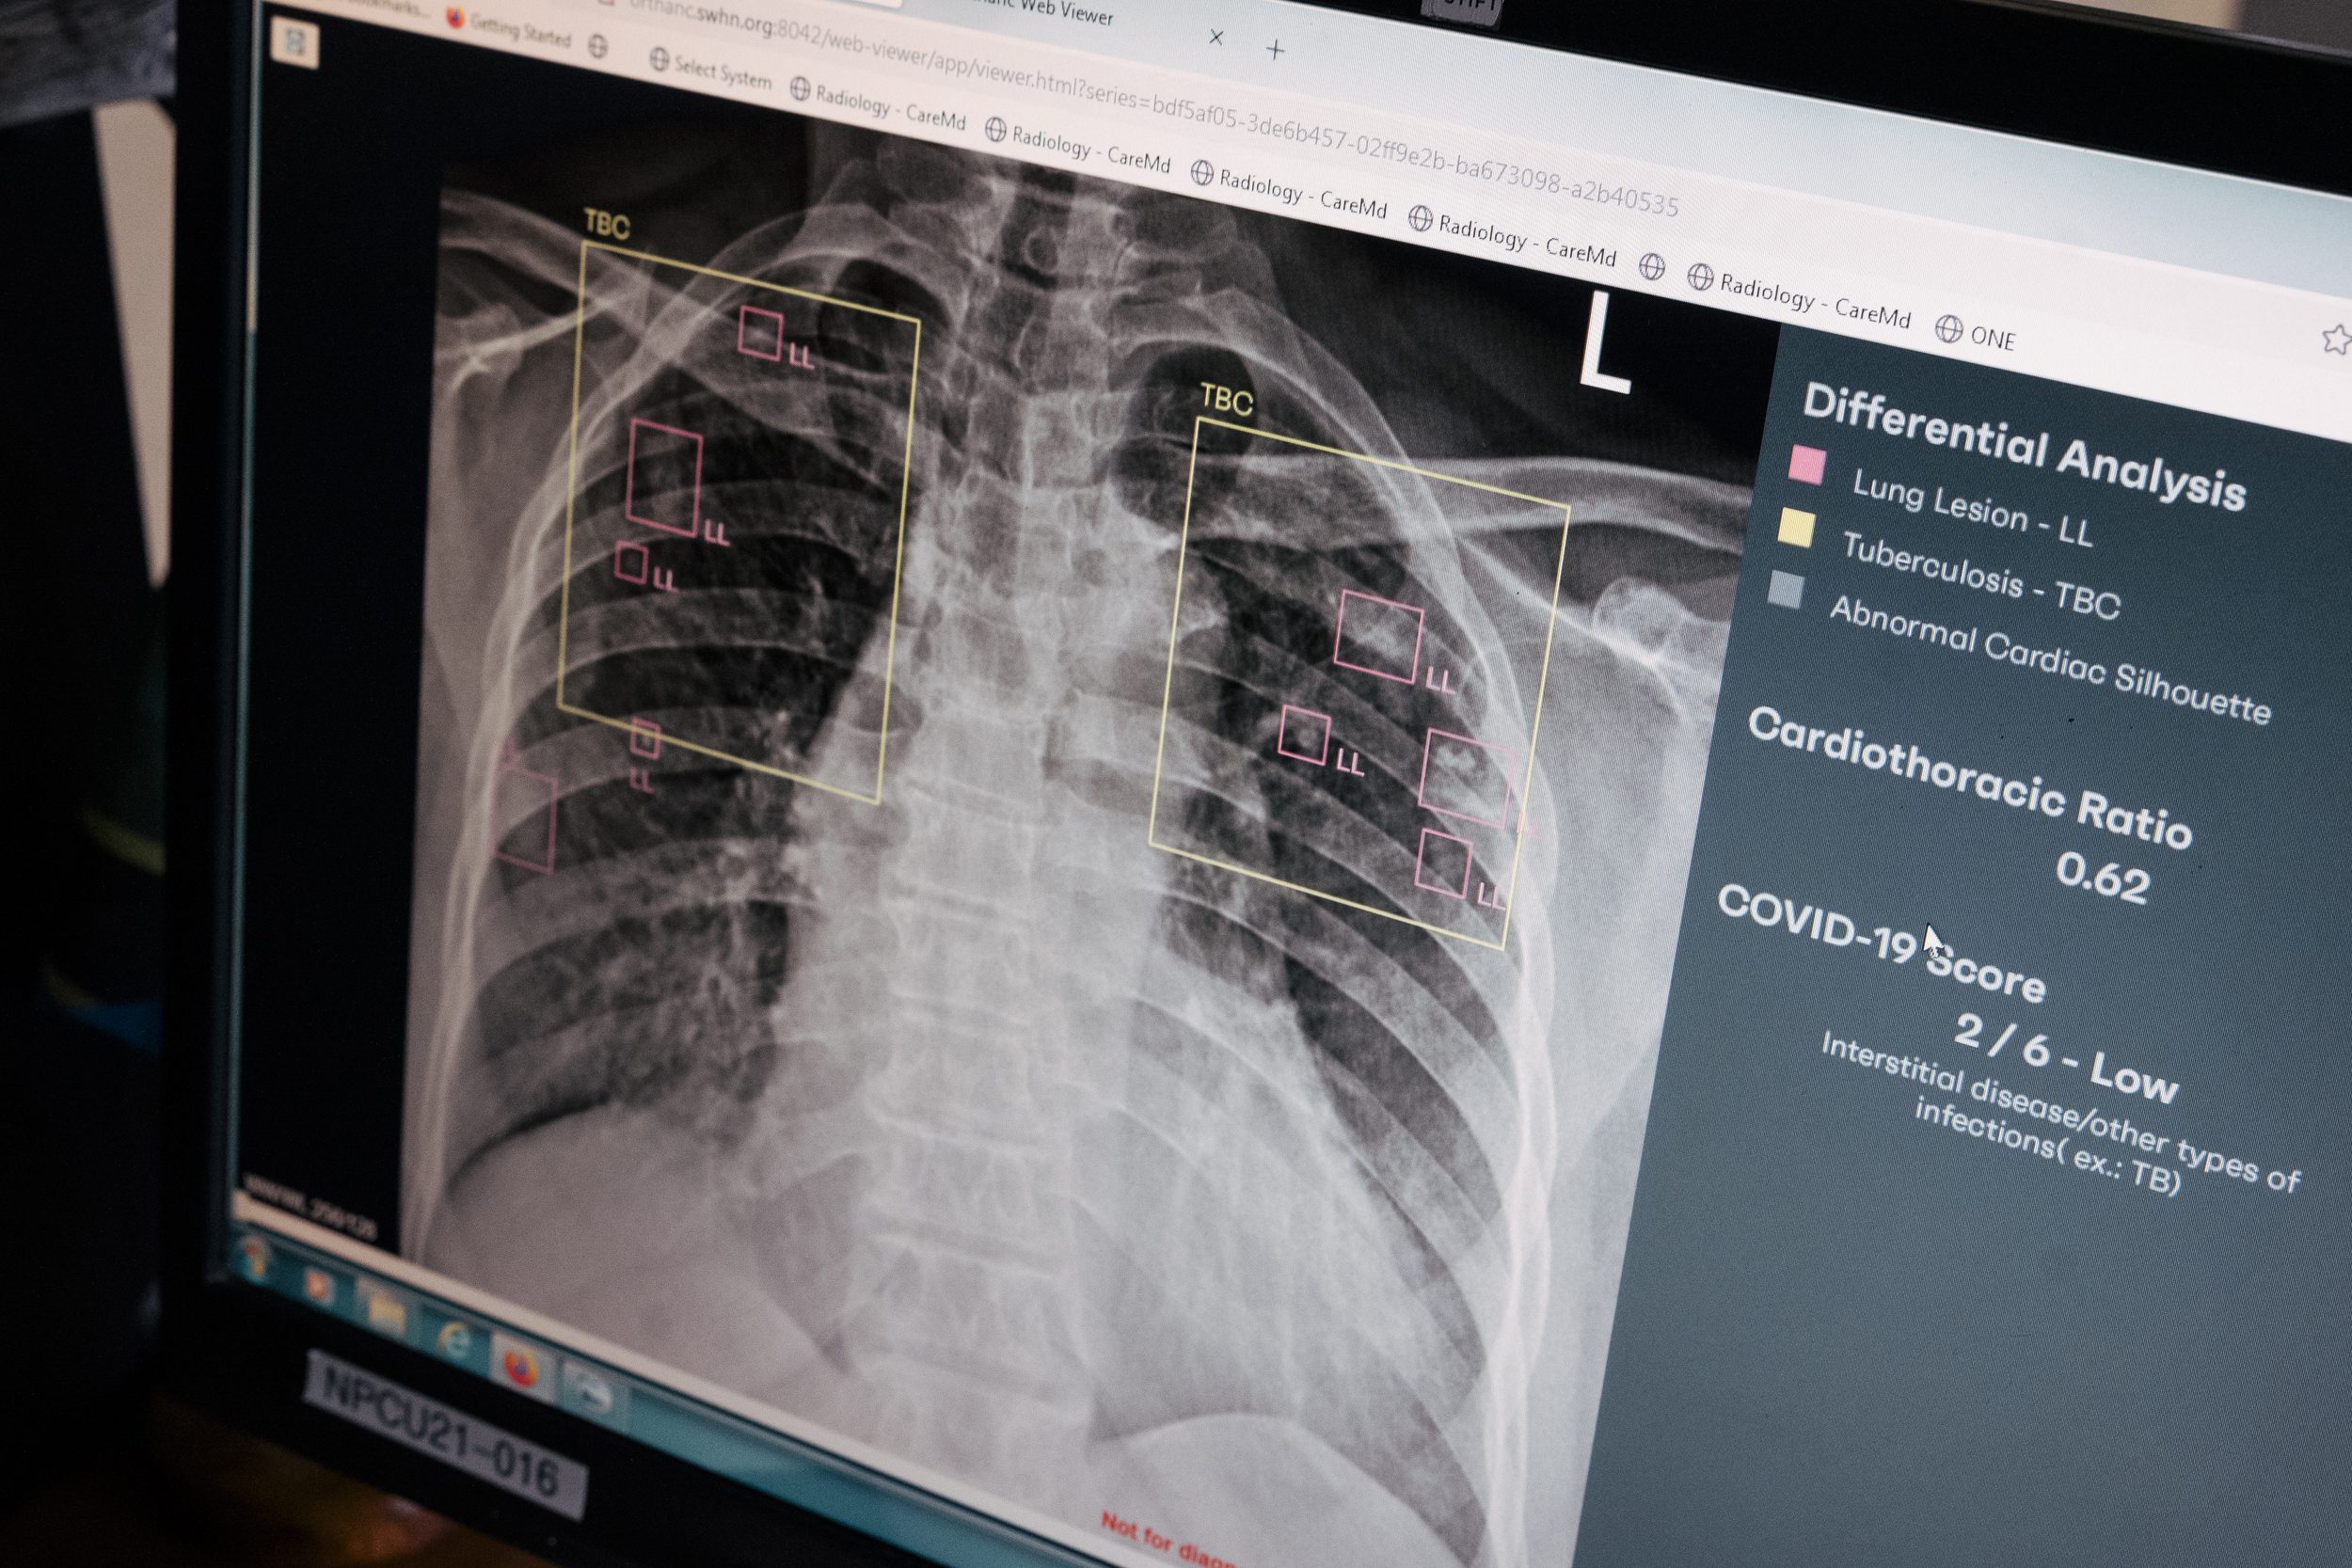

Seit 2025 gehen wir am St. Walburg’s Hospital neue Wege. Dank Dr. Amir Bigdeli, dem Chefarzt der Artemed Klinik München Süd, wurde in Zusammenarbeit mit unserem Partner deepc eine hochmoderne KI-Software der Firma Rayscape entwickelt und implementiert.

Diese künstliche Intelligenz ist ein digitaler Spezialist für die Lunge:

Die Software scannt Röntgenbilder und erkennt über 148 verschiedene Lungenerkrankungen.

Verdachtsmomente auf Tuberkulose werden sofort markiert.

Allein im März 2026 konnten dank der KI bereits mehr als 10 TB-Verdachtsfälle identifiziert werden, die sonst teils unentdeckt geblieben wären